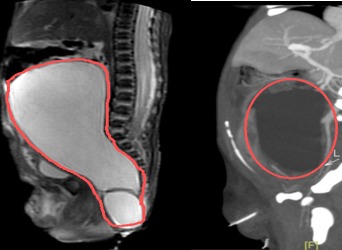

800克肿瘤“霸占”新生儿腹腔,多学科联手打赢生命第一战

在妈妈肚子里,萌萌(化名)就被发现骶尾部长了一个“大瘤子”——巨大的骶尾部畸胎瘤。这个肿瘤在她出生时已达800克,占据了大半个腹腔,挤压肠管,紧贴盆腔周围器官,生命伊始就面临严峻挑战。珠江医院多学科团队携手护航,通过高难度单孔腹腔镜微创手术,成功拆除了这颗“定时炸弹”,创造了生命的奇迹。产检惊现胎儿“腹中巨瘤”萌萌妈妈在孕34周的产检中,发现肚子里的宝宝屁股上长了个“大瘤子”,约10.1*5.3cm。随后,萌...